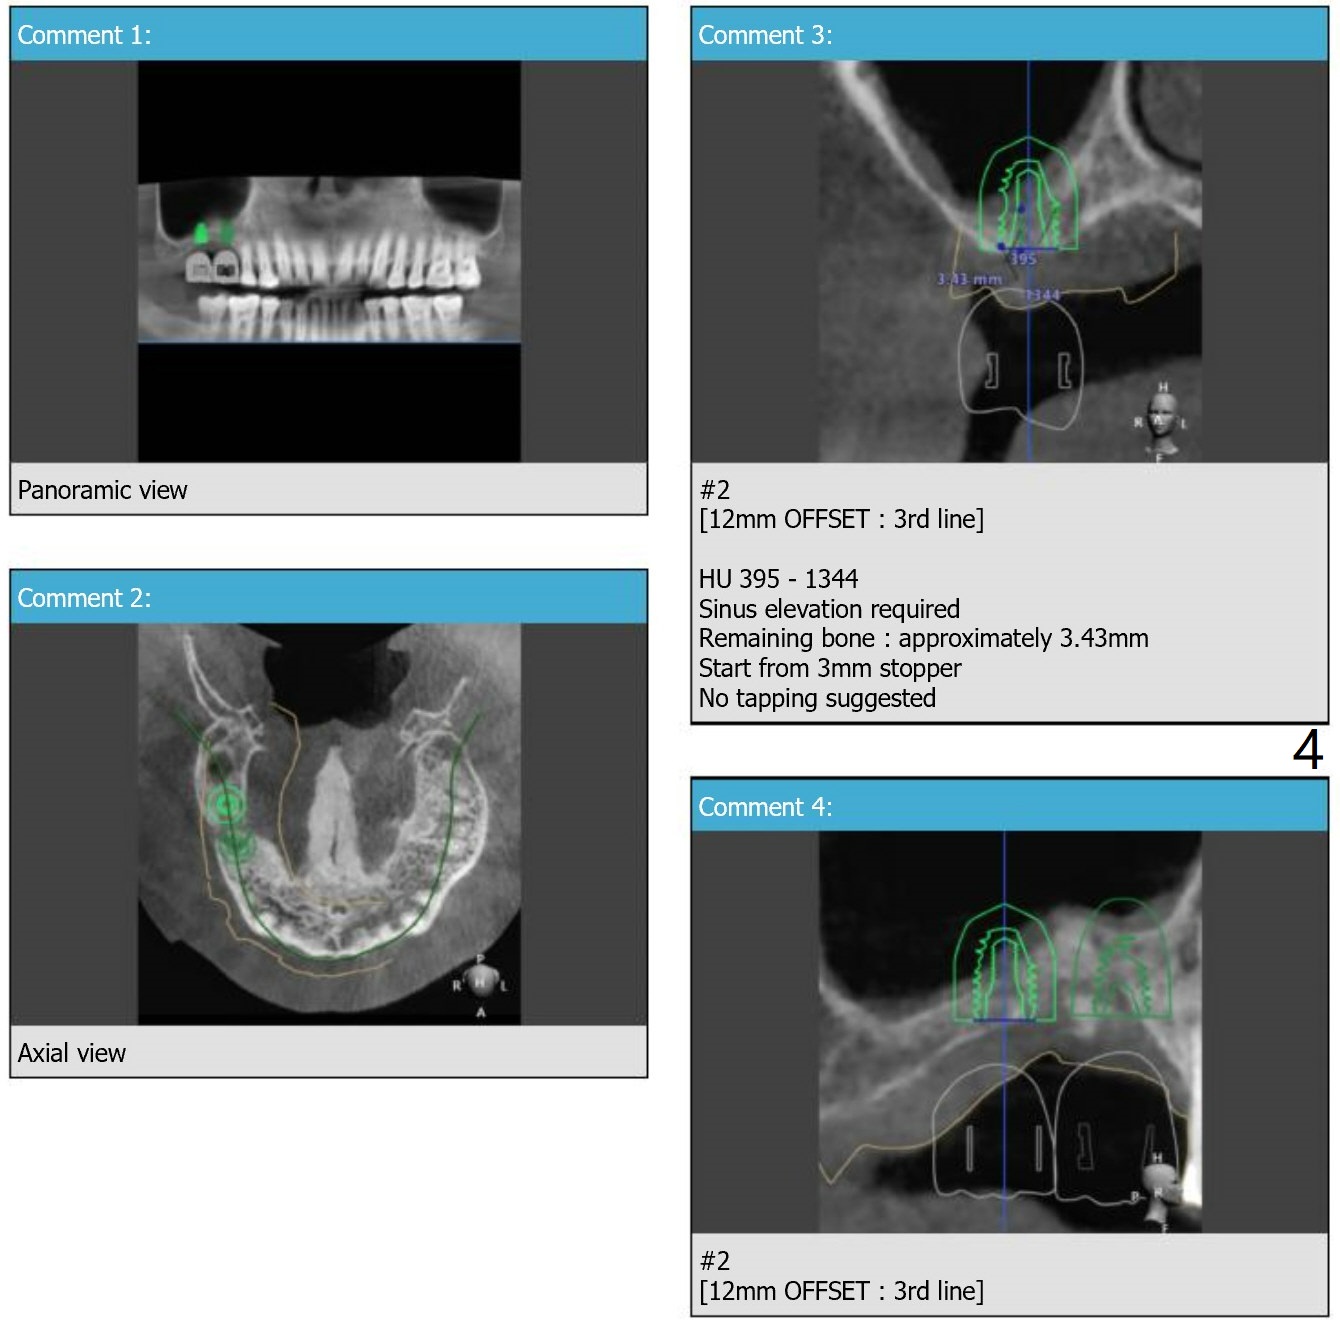

Short and Hard Bone

Return to Upper Molar Immediate Implant, Trajectory